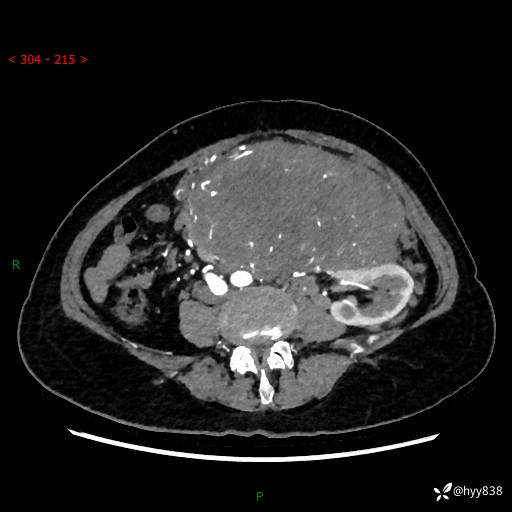

据说只有腹膜后,才能见到如此巨大的肿块---(有结果)

主诉:发现腹膜后占位1周

简要病史:患者1周前因头晕在当地第二人民医院检查发现左侧腹膜后区巨大富血供占位性病变,患者自诉腹部稍硬,无其他不适,无血尿,无腰痛等不适,患者为求进一步治疗来我院,门诊以“腹膜后占位性病变”收入我科。 起病以来,患者精神、饮食、睡眠可,大便正常,小便如上述,体力体重无明显改变。

临床诊断:腹膜后占位

腹部CT增强(动脉期+静脉期 ) ---平扫外院